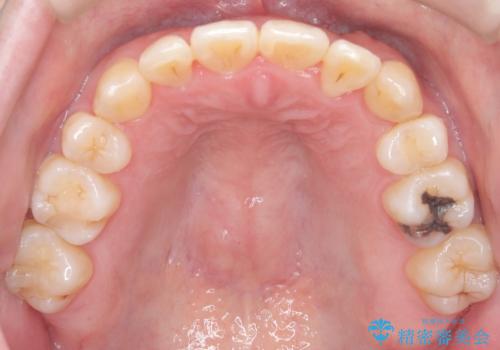

【重度叢生ワイヤー矯正】きれいな歯並びにしたい

- きれいな歯並びにしたいとの希望を持って来院された患者様です。

上下左右小臼歯を抜歯する治療計画を立て審美装置にて治療を行いました。

骨格的3級傾向もあり、咬合関係を仕上げるのに時間がかかりましたが、患者様には大変満足していただけました。

難しいケースでしたが、矯正用アンカースクリューを用いながら、臼歯関係もきれいに仕上げることができました。